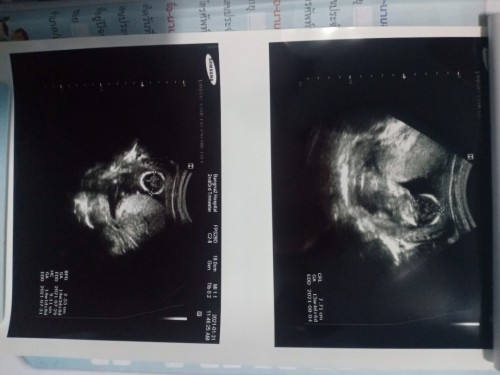

เมื่อวานเรามีเลือดปนออกมากับปัสสาวะเลยไปหาหมอ พอหมออัลตราซาวด์ให้เจอก้อนอะไรสักอย่างอยู่ในรกค่ะ หมอไม่แน่ใจว่าเป็นก้อนเลือดหรือก้อนเนื้อ คุณหมอที่เราฝากอยู่เขาเป็นหมอสูติทั่วไป เขาแนะนำให้ไปโรงเรียนแพทย์อย่างศริราช รามา ที่มีแพทย์เฉพาะทางอยู่ แต่เราอยู่สมุทรปราการ ซึ่งถ้าไปทางนู้นก็ค่อนข้างไกลอยู่ค่ะ อยากถามว่าแถวสมุทรปราการนี่มี รพ.ใหญ่ๆและมีหมอเฉพาะทางด้านนี้มั้ยคะ ถ้าไม่มีจริงๆก็คงต้องเลือกไป กทม. ค่ะ กลัวอันตรายต่อลูก 😭😭 #ขอคำแนะนำหน่อยค่ะ #ท้องแรกคะ #ขอบคุณสำหรับคำตอบค่ะ #ภาวะครรภ์เสี่ยง #ภาวะแทรกซ้อน